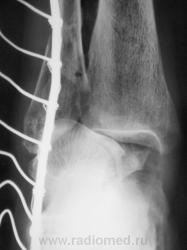

Перелом наружной и задней лодыжек. Подвывих в голеностопном суставе кнутри. Подвывих в тараннопяточном суставе. Разрыв дистального межберцового сочленения.

Переломы латеральной и медиальной лодыжек, пронационный подвывих в голеностопном суставе, латеральный подвывих в таранно-пяточном, разрыв межберцового синдесмоза.

Almo правильно задал вопрос, это касается терминологии. Про вывих стопы говорят, когда имеется вывих в г/ст суставе, а подтаранный N. Если имеется вывих в голенностопе и в подтаранном в противоположные стороны, т.е. смещается только таранная кость, говорят о вывихе таранной кости. Данный случай относится именно к последнему.